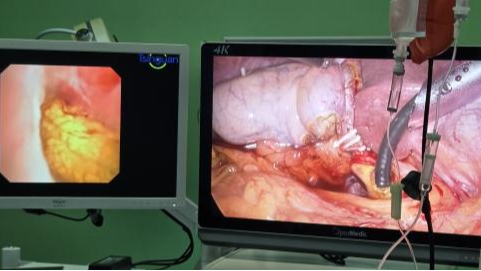

在麻醉团队的精准护航下,手术如期进行。术中,情况正如术前所料:患者腹腔内因既往手术布满了坚韧如革的粘连束带,正常解剖结构完全改变。手术团队凭借丰富的经验和精湛的技术,在腹腔镜下耐心、细致地一点点分解粘连,如同在迷宫中开辟出一条安全通道。成功显露胆总管后,医生们精准切开,将堵塞在胆总管下段的大量形态各异的结石悉数取出,彻底解除了梗阻。术中放置了T管以确保术后胆汁引流通畅,并同期切除了病变的胆囊,从根源上杜绝了结石复发的隐患。整台手术仅在腹部留下几个微小孔洞,出血量极少,创伤大幅降低。